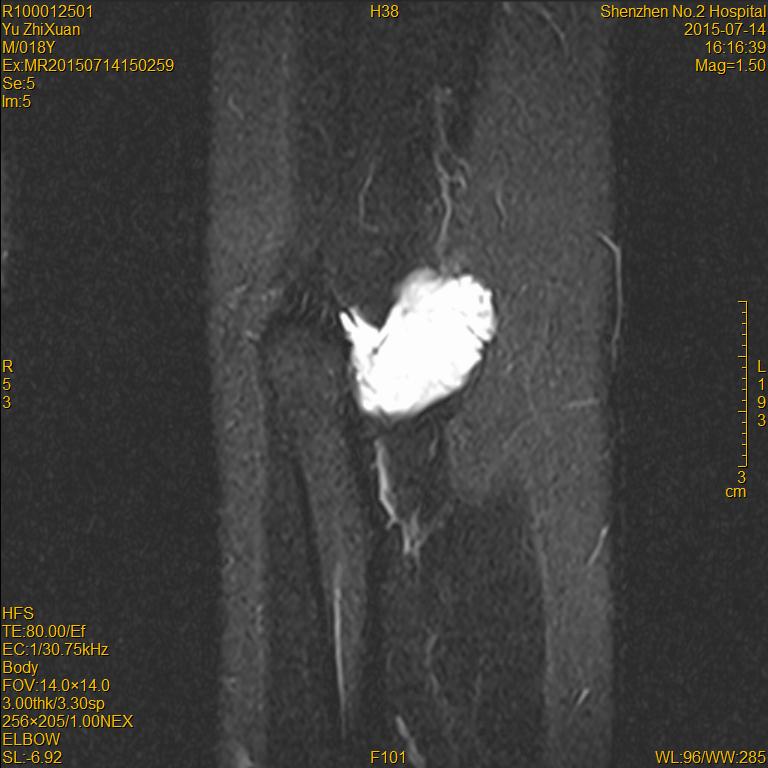

MR检查

( 增强 )